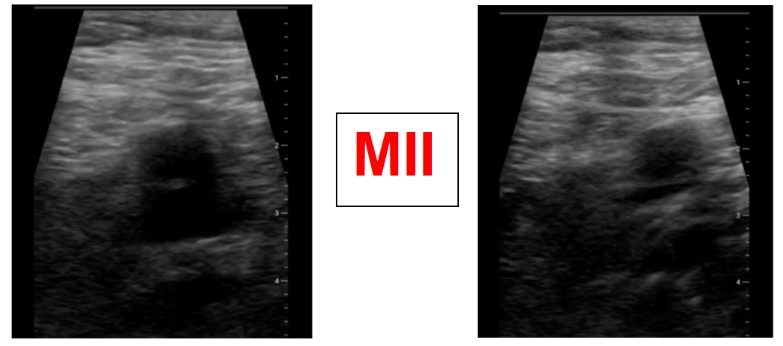

Ante la sospecha de Trombosis venosa profunda realizamos ecografía de compresión venosa de miembros inferiores detectando la falta de colapsabilidad de la femoral común y femoral superficial del miembro inferior derecho, cosa que no pasaba en el izquierdo.